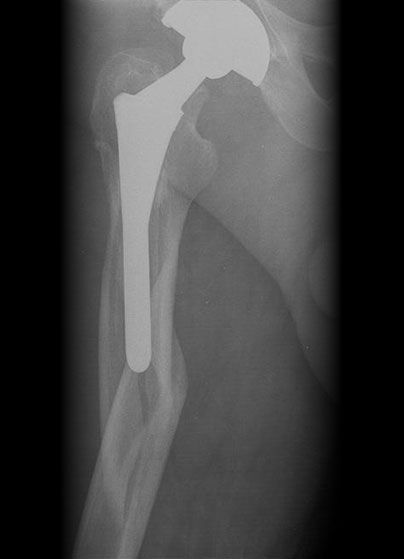

Failed TKR

Failed THR